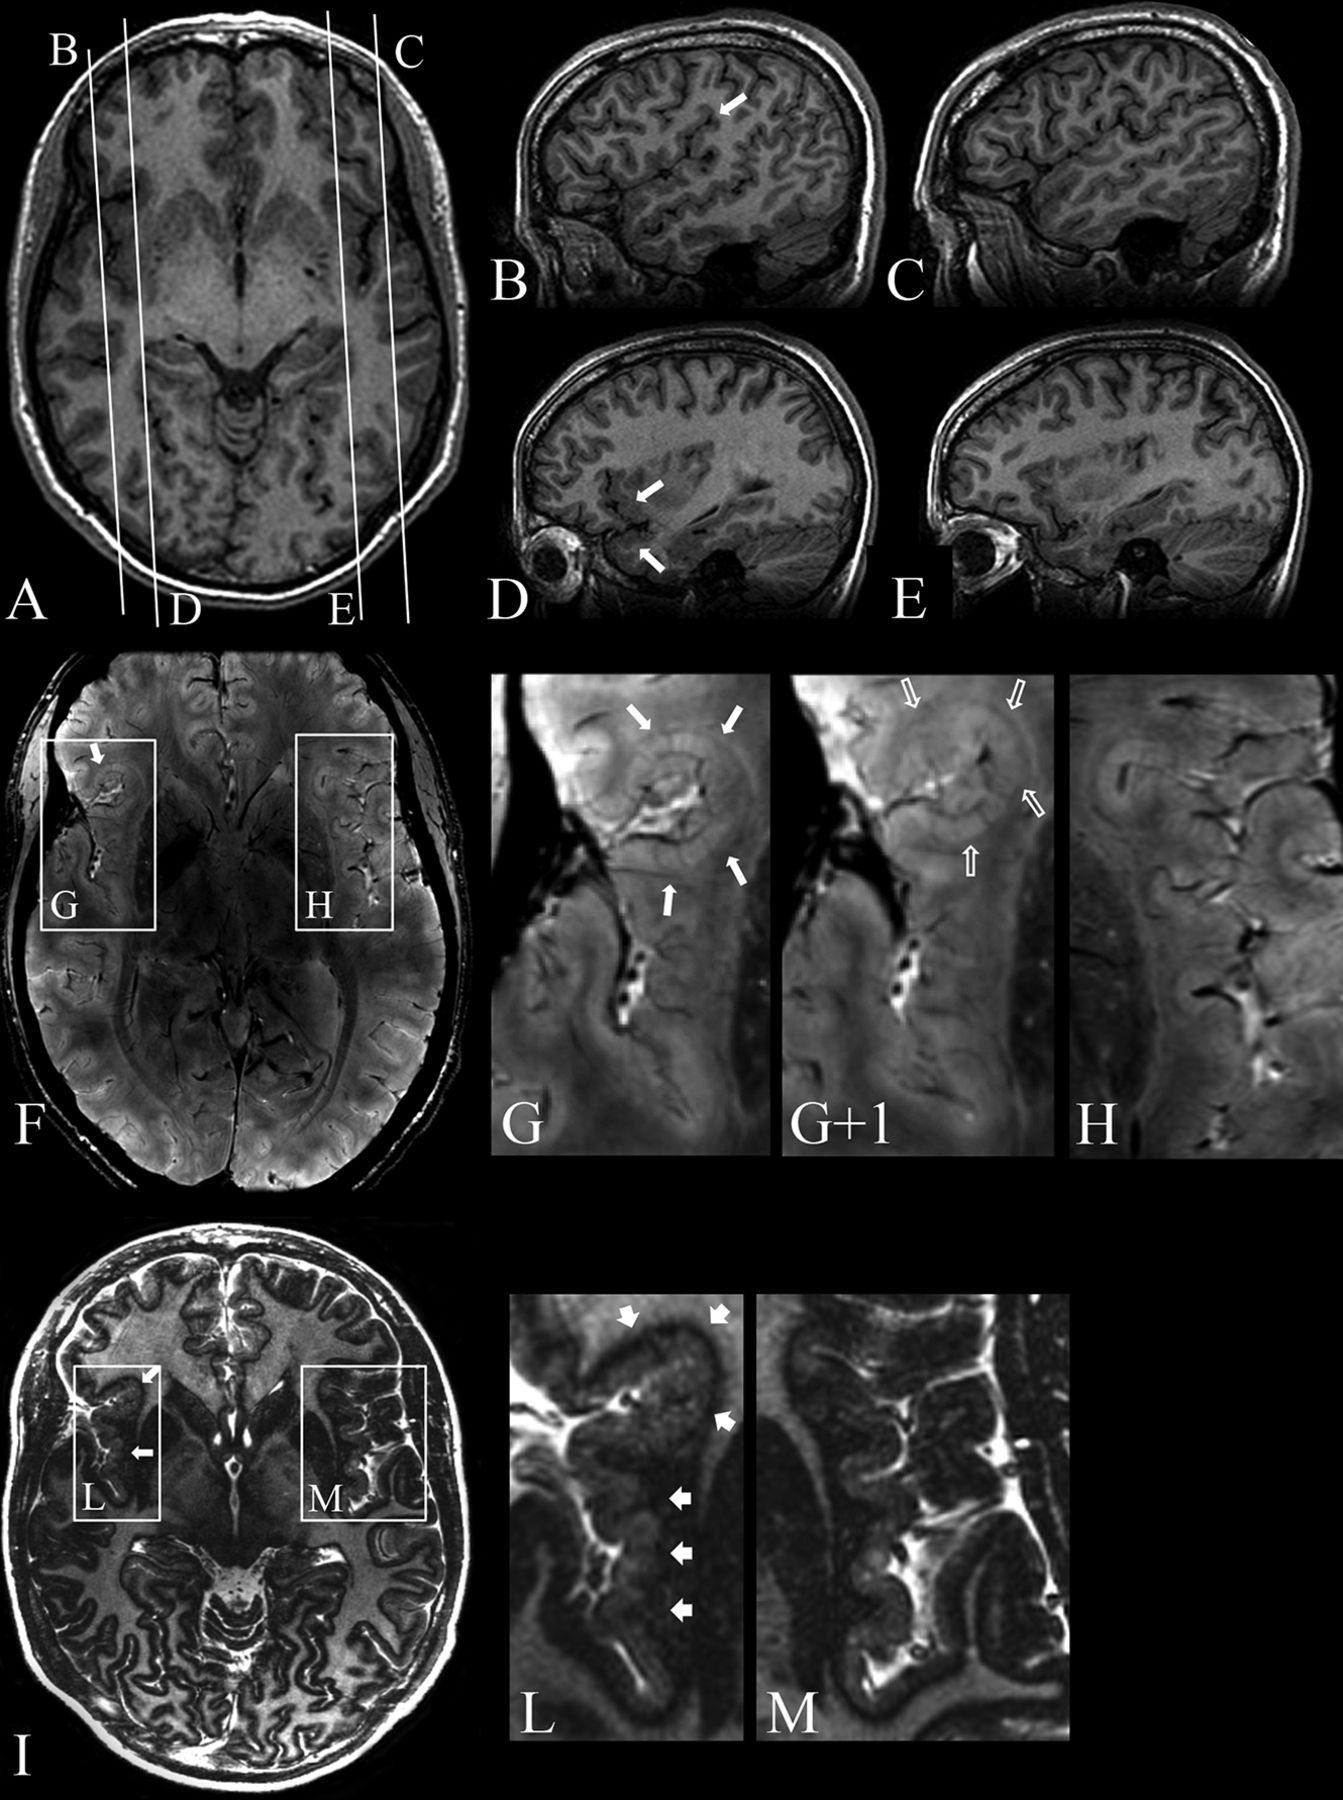

At 3T, we observed perisylvian polymicrogyria that was unilateral in 7 patients and bilateral in 2. Of the 7 patients with unilateral polymicrogyria, 6 had multilobar involvement, and in 1, only a portion of the Sylvian fissure was involved (Fig 1). One patient had diffuse polymicrogyria.

Patient 8. 3T axial (A) and sagittal (B–E) 3D FSPGR, 7T 3D SWAN (F), and magnified images (G, G+1, H), 7T axial 2D TBE FSE-IR (I) and magnified images (L and M). A, Mild cortical thickening in the right frontal operculum. Contiguous sagittal sections across the frontal operculum and the Sylvian fissure on the right (B and D) and left (C and E) sides provide a better comparative view of the morphologic characteristics of malformed-versus-normal cortex. B, An abnormal right Sylvian fissure (arrow), which is vertically oriented, shortened, and bordered by thick and irregular cortex. D, Thickening of the cortex in the inferior frontal gyrus and superior temporal gyrus (arrows). F, Two contiguous expanded views, from caudal (G) to rostral (G+1), provide ultra-high-resolution details of the right frontal operculum, which are not visible at 3T (A–E), substantiating the presence of a polymicrogyric cortex. H, A magnification of the homologous contralateral region clearly enhances the appreciation of the difference in folding of the polymicrogyric and normal cortex. I, Magnifications (L and M) show a hypointense line representing the gray-white matter interface and provide a high definition of the polymicrogyric (L, arrows) and normal (M) cortex, making it easier to appreciate irregularities in thickness and folding of the polymicrogyric cortex.

7T provided additional details to 3T findings and revealed more extensive areas of polymicrogyria in all patients. In particular, in 3 patients (patients 4, 7, and 8) in whom 3T FSPGR imaging had revealed unilateral polymicrogyria, 7T SWAN imaging confirmed a unilateral distribution but detected more extensive involvement (Fig 1). In 3 patients with bilateral polymicrogyria at 3T (patients 1, 3, and 9), 7T SWAN revealed more extensive involvement. Four patients (patients 2, 5, 6, and 10) who had been classified as having unilateral polymicrogyria at 3T exhibited bilateral involvement at 7T (On-line Fig 2). In patient 2, 3T FSPGR showed left posterior polymicrogyria engaging the left temporoinsuloparietal region and the medium and superior occipital gyri. 7T SWAN imaging disclosed that polymicrogyria also involved the right posterior insula. In patient 5, in whom 3T FSPGR showed left frontotemporoparietal polymicrogyria along the whole Sylvian fissure, 7T SWAN revealed polymicrogyria also in the right frontal operculum. In patients 6 and 10, the polymicrogyric cortex had right temporoparietal distribution at 3T FSPGR, while 7T disclosed abnormal infolding and thickening of the left frontal operculum. In patient 10, 7T SWAN also showed that polymicrogyria involved the area around the whole left Sylvian fissure, left anterior insula, and left anterior temporal region.

In all patients, TBE imaging revealed a hypointense line corresponding to the gray-white matter interface, providing a high definition of the borders of the polymicrogyric cortex (On-line Figs 3 and 4). TBE imaging substantiated SWAN findings and, providing a precise topographic definition of the gray-white matter junction, made the examiner more confident about the extent of polymicrogyria, especially when the border between gray and white matter was poorly defined or the polymicrogyric cortex merged with a seemingly normal cortex (On-line Figs 3 and 4).